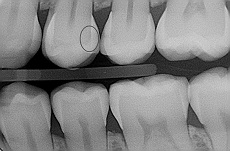

b) snímek k detekci – zjištění mezizubních kazů (anglicky: bite wing) - zobrazuje nově vzniklé kazy v mezizubním prostoru, kvalitu již zhotovených výplní, druhotné kazy vznikající v okolí výplní. Provádějí se od trojek dozadu (čili 4-8 na každé straně v horní i v dolní čelisti), kde je v sousedství zubů široký sklovinný val, přes který mnohdy kaz není v počátečních stádiích vidět nebo je lehce přehlédnutelný.

Foto 3-5: Pořízení snímků ke zjištění mezizubních kazů, které jsou označeny kroužkem.